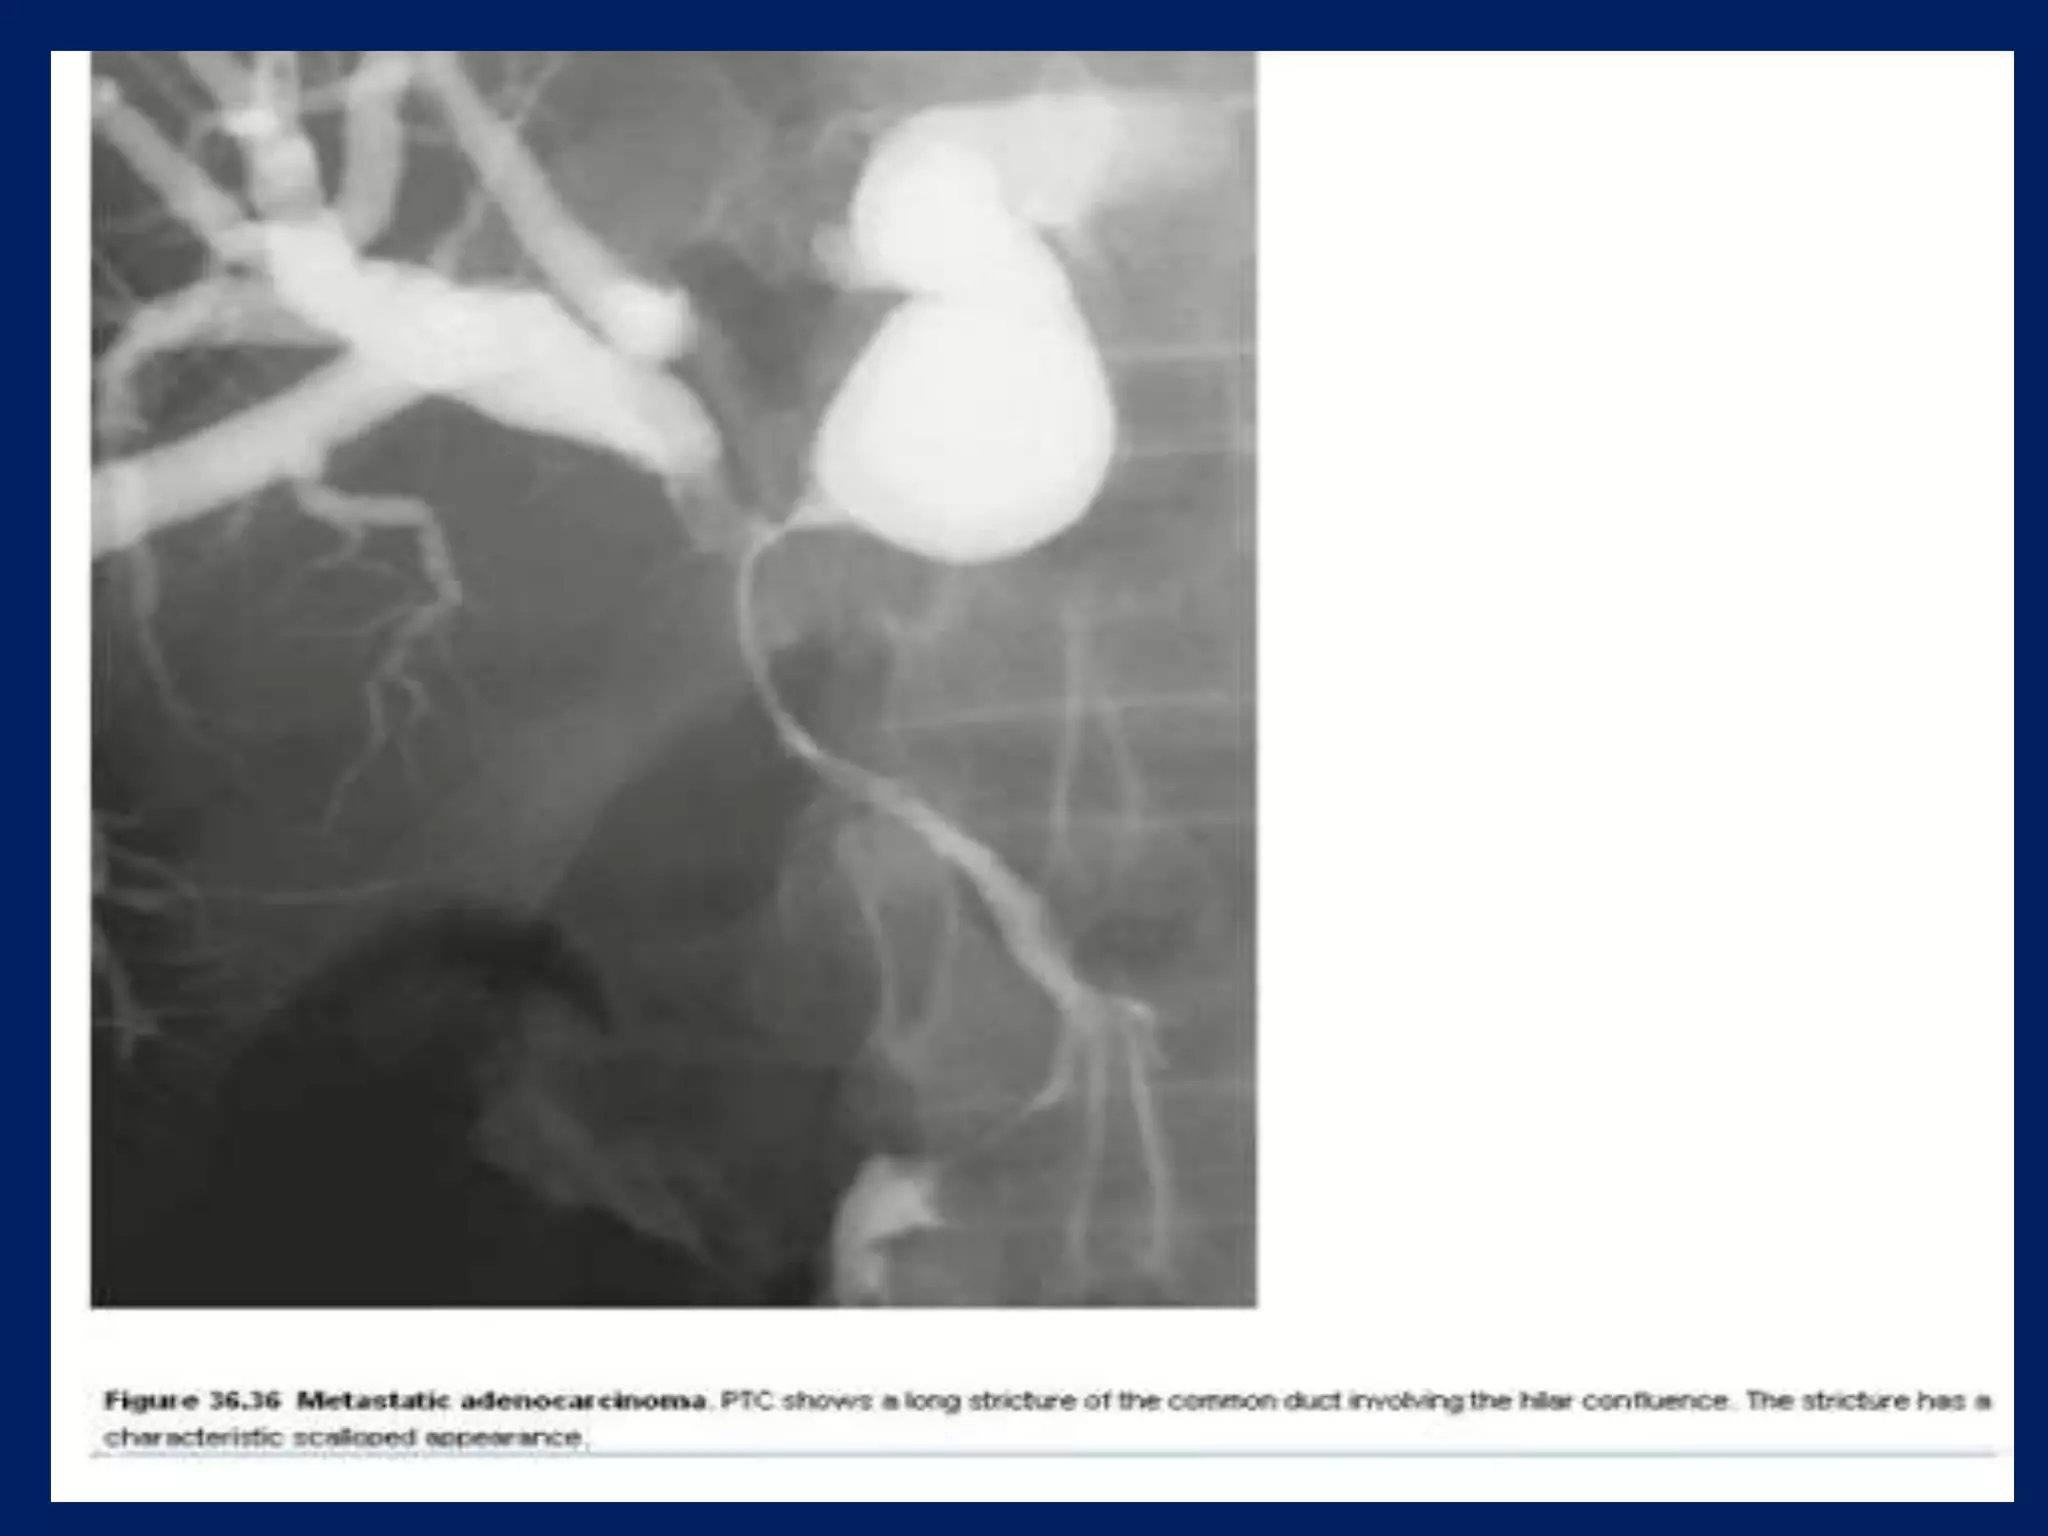

This document discusses imaging techniques for evaluating the biliary system. It covers common bile duct stones and Mirizzi's syndrome, which involves compression of the common bile duct by gallstones. It also mentions biliary cystadenoma, a type of cyst forming in the bile ducts or gallbladder.